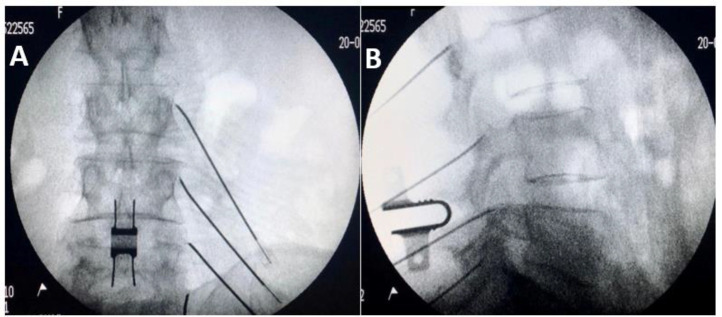

Lumbar medial branch radiofrequency ablation. (A) AP view with RF cannulae at SAP/TP junction — the electrode must be parallel to the medial branch nerve for maximal lesion coverage. (B) Lateral view confirming position.

2. Level identification: AP fluoroscopy to identify target transverse processes at each level

3. Electrode placement: The RF electrode (typically 18-22 gauge cannula with active tip) must be placed PARALLEL to the medial branch nerve along the junction of the transverse process and SAP

5. Confirm position: AP and lateral fluoroscopy

IPSIS Lumbar RFN Technique Details

Cannula Trajectory and Placement

• 15-20 degrees ipsilateral obliquity helps avoid the mamillo-accessory ligament (MAL) when positioning the cannula alongside the nerve

• Excessive obliquity (25-30 degrees) results in a more transverse approach that is less parallel to the nerve and less effective

• A declined fluoroscopic tilt of approximately 35-40 degrees is required to parallel the nerve as it crosses the lateral SAP base

• True lateral imaging establishes cannula depth: the active tip should overlie the middle two-fourths of the lateral SAP for L1-4 medial branches

• For the L5 dorsal ramus, the cannula should be over the posterior two-thirds of the S1 SAP

Lumbar Lesion Parameters

• Temperature: 80-85 degrees C for 90 seconds

• Lumbar: 15-20 degrees ipsilateral obliquity + 35-40 degrees declination parallels the cannula to the nerve at the SAP base (IPSIS)

• Lumbar lesion zone: middle two-fourths of SAP for L1-4; posterior two-thirds of S1 SAP for L5 DR — avoid ventral and posterior extremes (IPSIS)